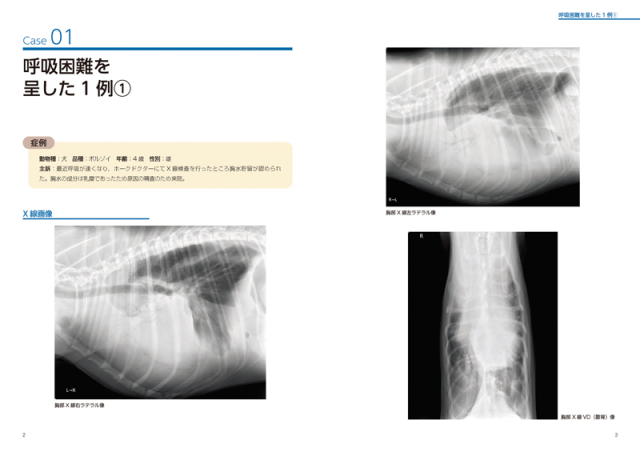

「思考プロセスを習得する犬と猫のX線読影」定価:17,600円新品無使用を裁断しました。書き込み等はありません。値下げは行いません。